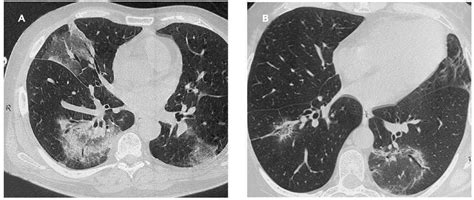

Patrones de presentación de la neumonía organizada ...

Patrones de presentación de la neumonía organizada ... from multimedia.elsevier.es

Hallazgos radiológicos de la neumonía por virus herpes ...

Hallazgos radiológicos de la neumonía por virus herpes ... from scielo.isciii.es